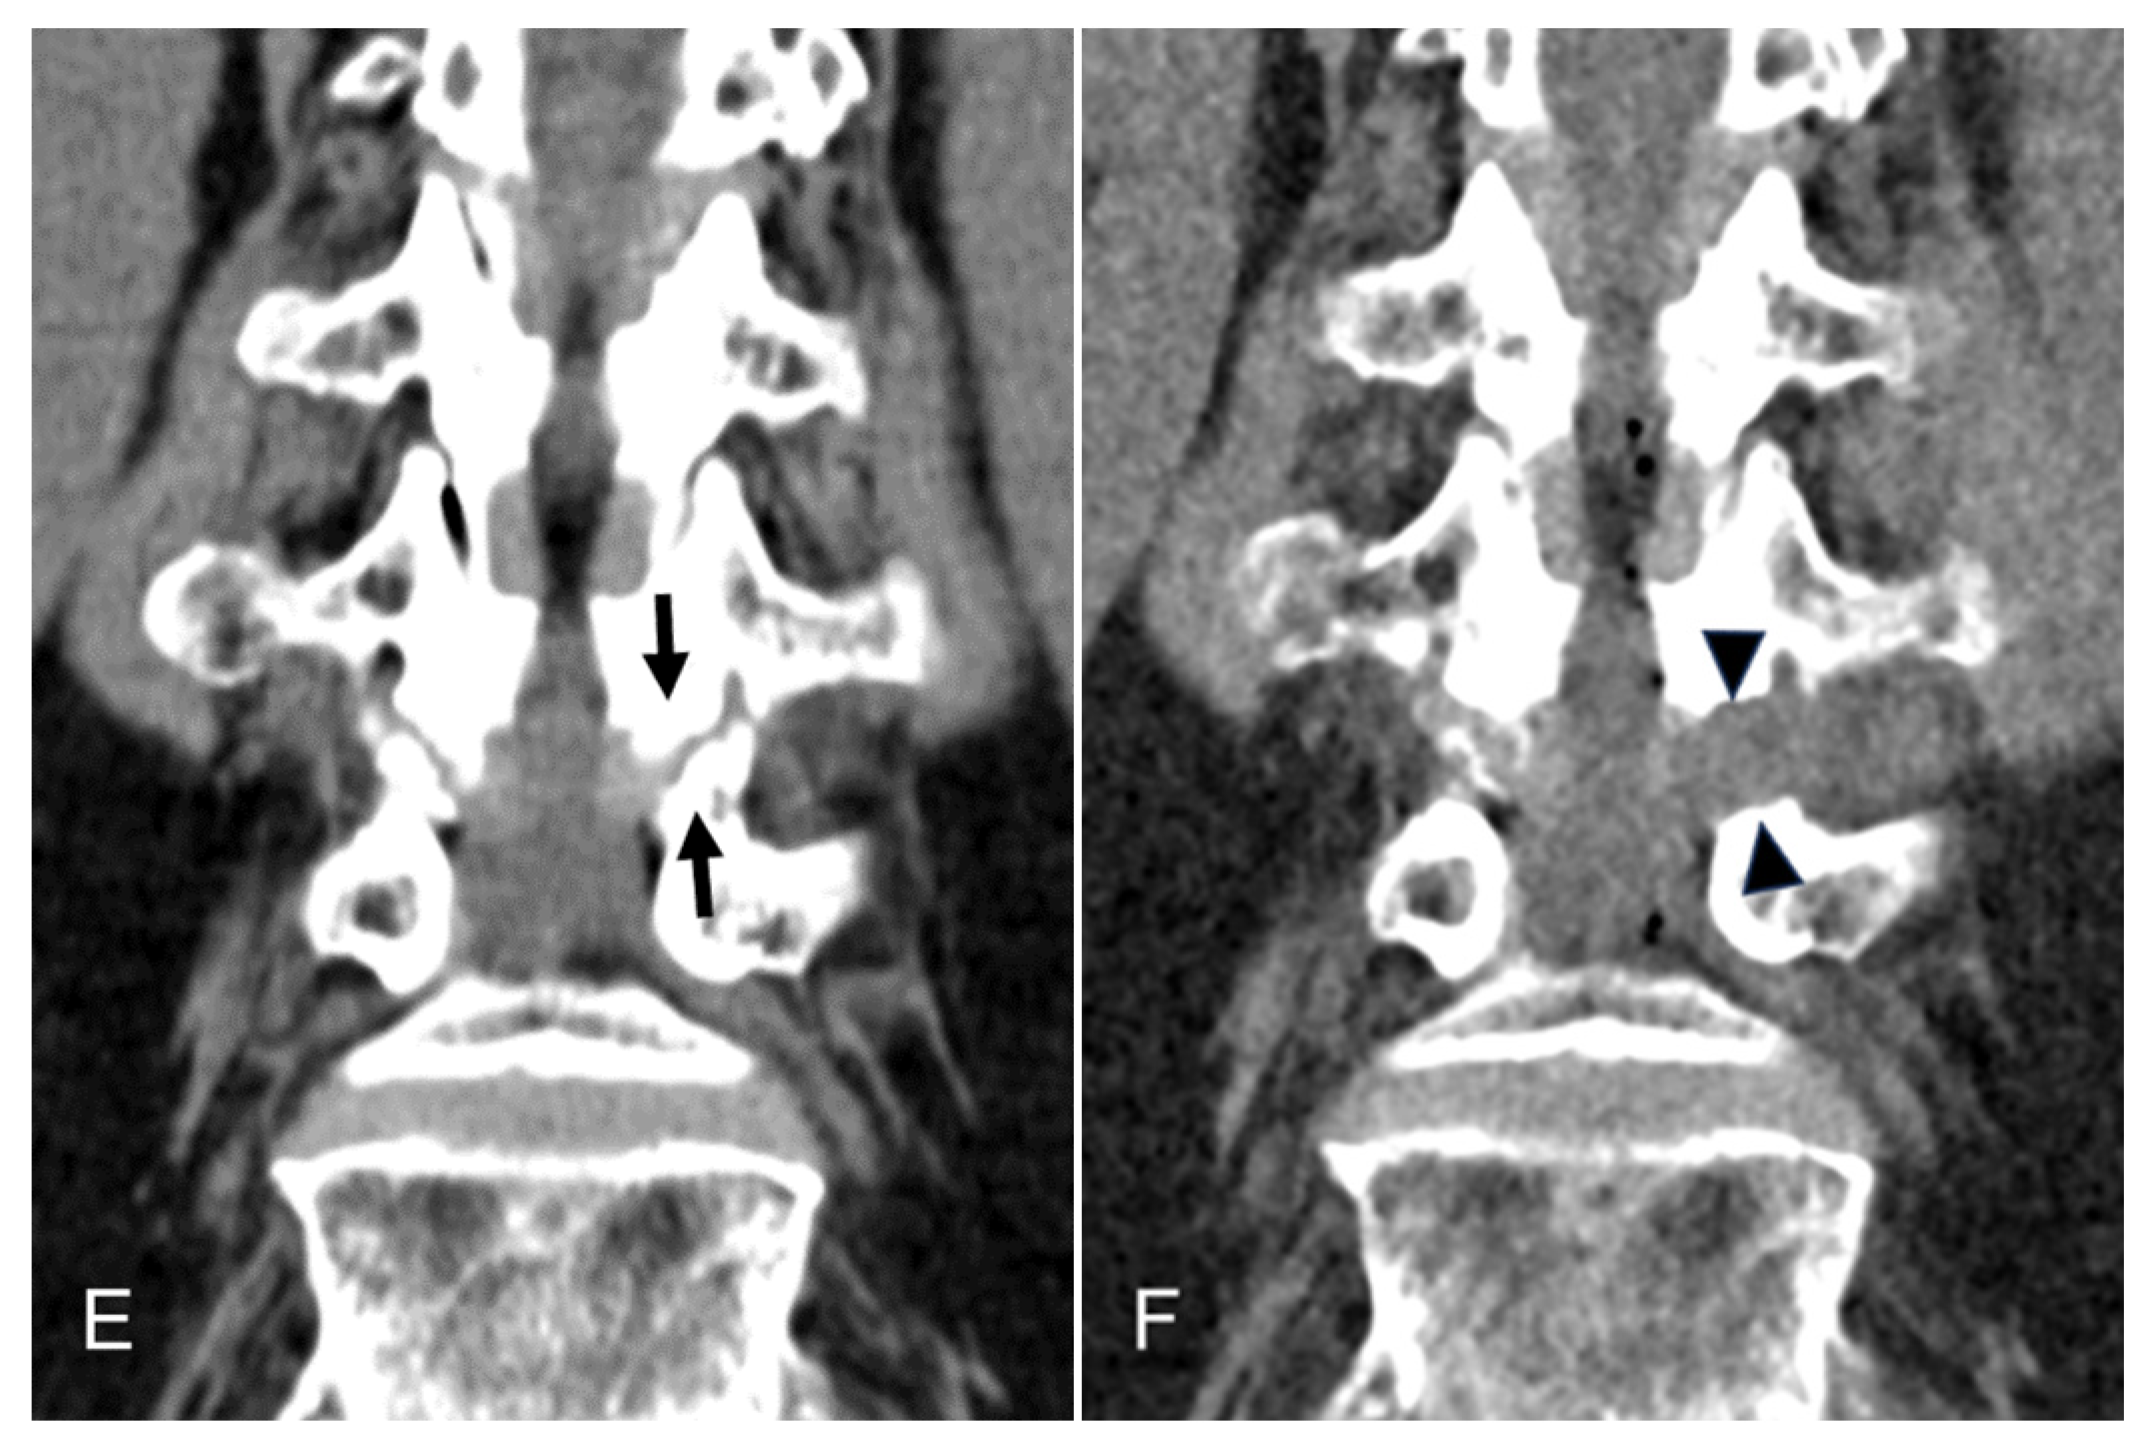

Figure 2.

Intraoperative endoscopic pictures TELLRD. (A) Bony unroofing using endoscopic burrs and punches. The hypertrophic SAP and part of the pedicle were undercut using an endoscopic burr (L4–L5, left). (B) Ventral decompression with removal of thickened LF using endoscopic punches. (C) Dorsal decompression with removal of redundant disc and shoulder osteophytes using endoscopic burrs and punches. (D) Final endoscopic view showing the released TNR. TELLRD, transforaminal endoscopic lumbar lateral recess decompression; SAP, superior articular process; LF, ligamentum flavum; TNR, traversing nerve root.